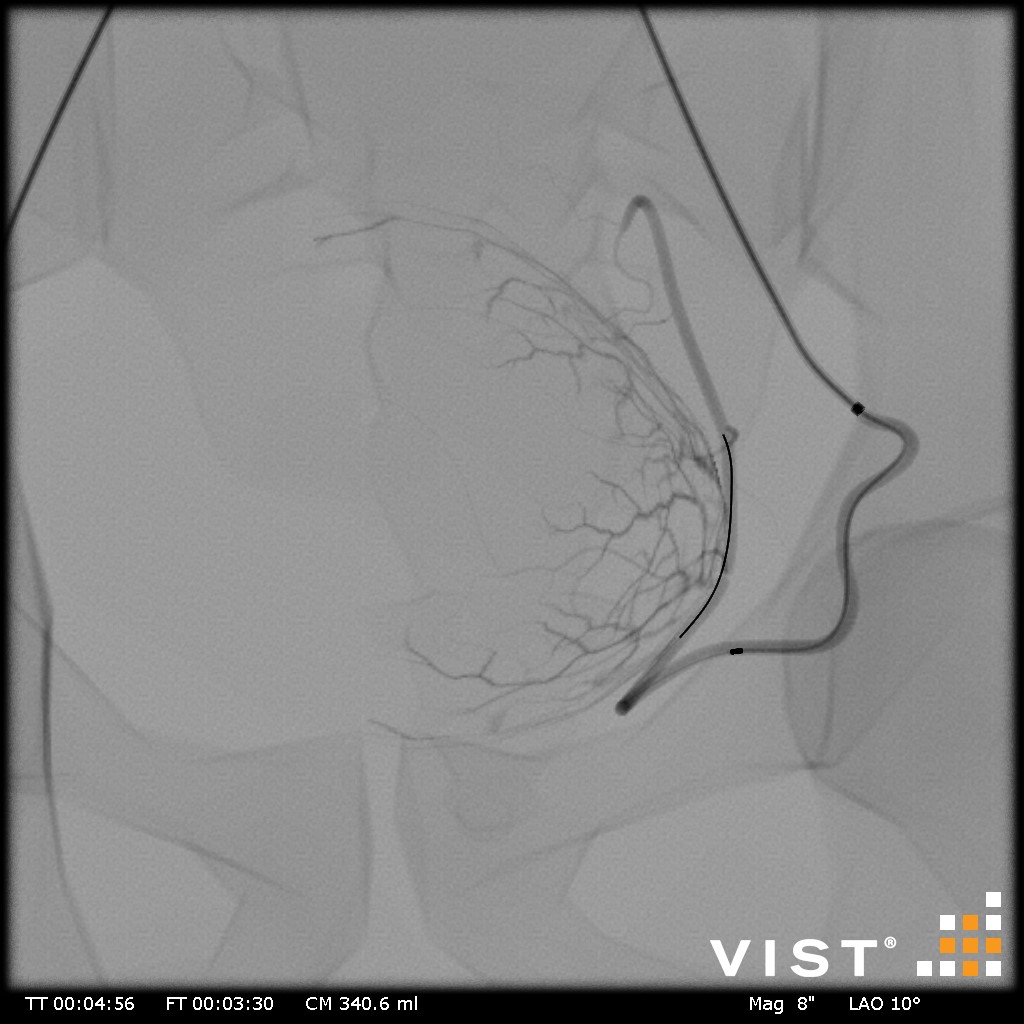

Simuladores Endovanculares.

Aquíhayuna listademódulosundonibles concatibles con el simulador vist g5(Versiónforporidenteyy lab,没有兼容的孔血管y vist灯)。Esta listaestántancoreeevolución,没有Dude en advertarla promicy ... los dutallesestándisponibles haciendo clic en eltítulodelmódulo(网站蒙黛尔,enInglés)